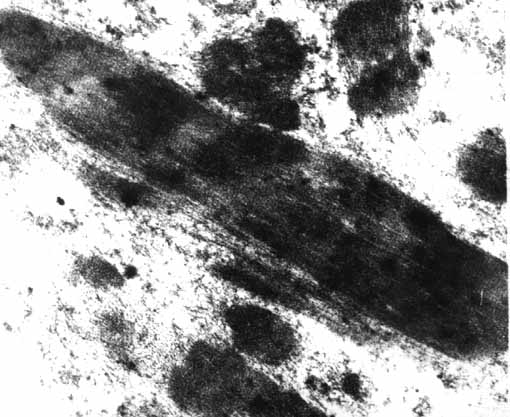

Fig.6: Bandas electrondensas elongadas, osmiofílicas, similares al material de banda Z. MEX15k.

Fig.7: Id , MEX30k.